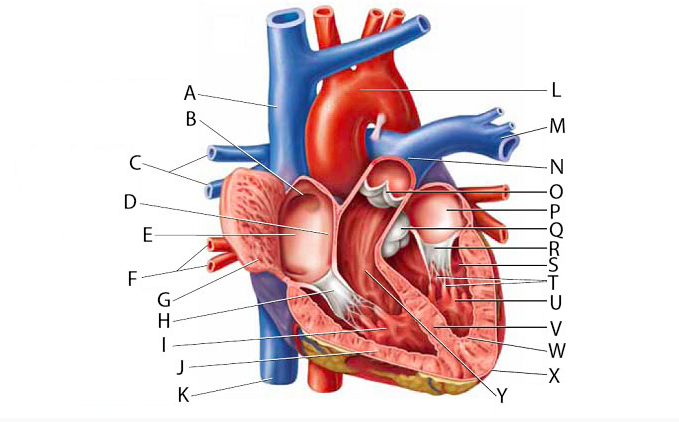

Anterior interventricular valve

Anterior interventricular sulcus

Posterior interventricular sulcus

Aortic Arch

Aortic Valve (=left semilunar)

Apex (of the heart)

Ascending/descending aorta

Brachiocephalic artery

Brachiocephalic vein

Chordae tendineae

Circumflex branch (of the left coronary artery)

Coronary sinus

Endocardium

Epicardium

interventricular branch of the left coronary artery. = left anterior descending artery (LADA))

Left atrioventricular (=bicuspid, =mitral) valve

Left/right atrium

Left/right auricle

Left/right coronary artery

left/right pulmonary artery/vein

left/right ventricle

Myocardium

Papillary muscles

Pectinate muscles

Pericardial sac (=fibrous pericardium)

Pulmonary trunk

Pulmonary valve (=right semilunar)

Right atrioventricular (=tricuspid) valve

Superior/inferior vena cava